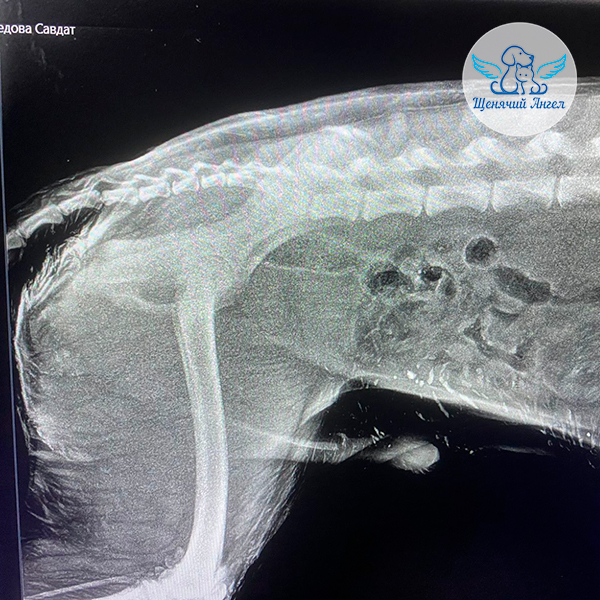

🕊 Друзья, делимся новостями о щенке Севере, которого сбили на дороге в селе рядом с Буйнакском 🚗💔.

Благодаря вашей помощи Севера удалось экстренно госпитализировать в местную ветеринарную клинику 🏥, где ему провели инфузионную терапию и сняли выраженный болевой синдром 😖, из-за которого щенок был практически полностью обездвижен. После стабилизации состояния Севера мы перевезли в Москву, в ветеринарный центр «Юна» для дальнейшей диагностики 🧫🔬.

📋 В клинике щенку выполнили все необходимые обследования: сдали анализы, сделали УЗИ и рентген 🩻 . К счастью, серьёзных патологий не выявлено 🙏🏻. Однако у него сохраняются трудности с опорой на задние лапы 🐾.

Для уточнения причины Севера осмотрел ортопед 👨🏻⚕, но осмотр оказался затруднён из-за выраженной стрессовой реакции и агрессии при манипуляциях 😔.

Также у щенка на бедре выявлен участок гиперемии, похожий на начинающийся пролежень. Все повреждения обработаны и находятся под контролем врачей 👩🏼⚕.

На данный момент наша основная задача – дождаться снижения уровня стресса у Севера и стабилизации его поведения. Это позволит провести полноценное дополнительное обследование и уточнить дальнейший план лечения ❤🩹.

Огромное спасибо каждому из вас за поддержку, участие и добро, которое помогло спасти Северу жизнь 🫶🏻. Вместе мы делаем всё возможное, чтобы малыш как можно скорее вернулся к нормальной жизни без боли и страха 🐶🍀.